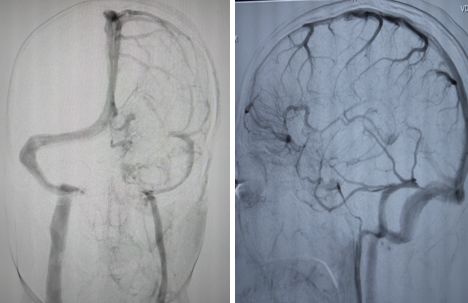

病例10

患者男性,40岁,头痛2天。

答案:脑静脉畸形

脑静脉畸形最佳诊断要点是“海蛇头”(曲张的白质内静脉)。最常见部位是脑室额角或者临近第四脑室处,大小各异、但通常<3cm。曲张的静脉呈伞样集合,大的“集合”静脉引流进入硬膜静脉窦或深部室管膜静脉。增粗的“集合”静脉在CT可呈高密度,如果为混合海绵状血管畸形,可存在钙化。MRI上如果DVA小,可能表现正常,因大小、血流量的不同而信号各异,可有血液流空,通常显著强化。